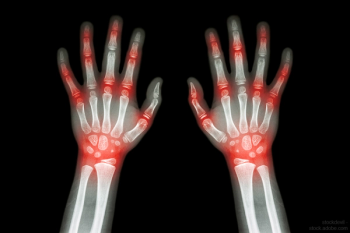

The latest in RA therapies, and what you can expect from the pipeline.

FDA is warning about an increased risk of death and blood clots in the lungs in patients with rheumatoid arthritis taking a specific dosage of this drug.